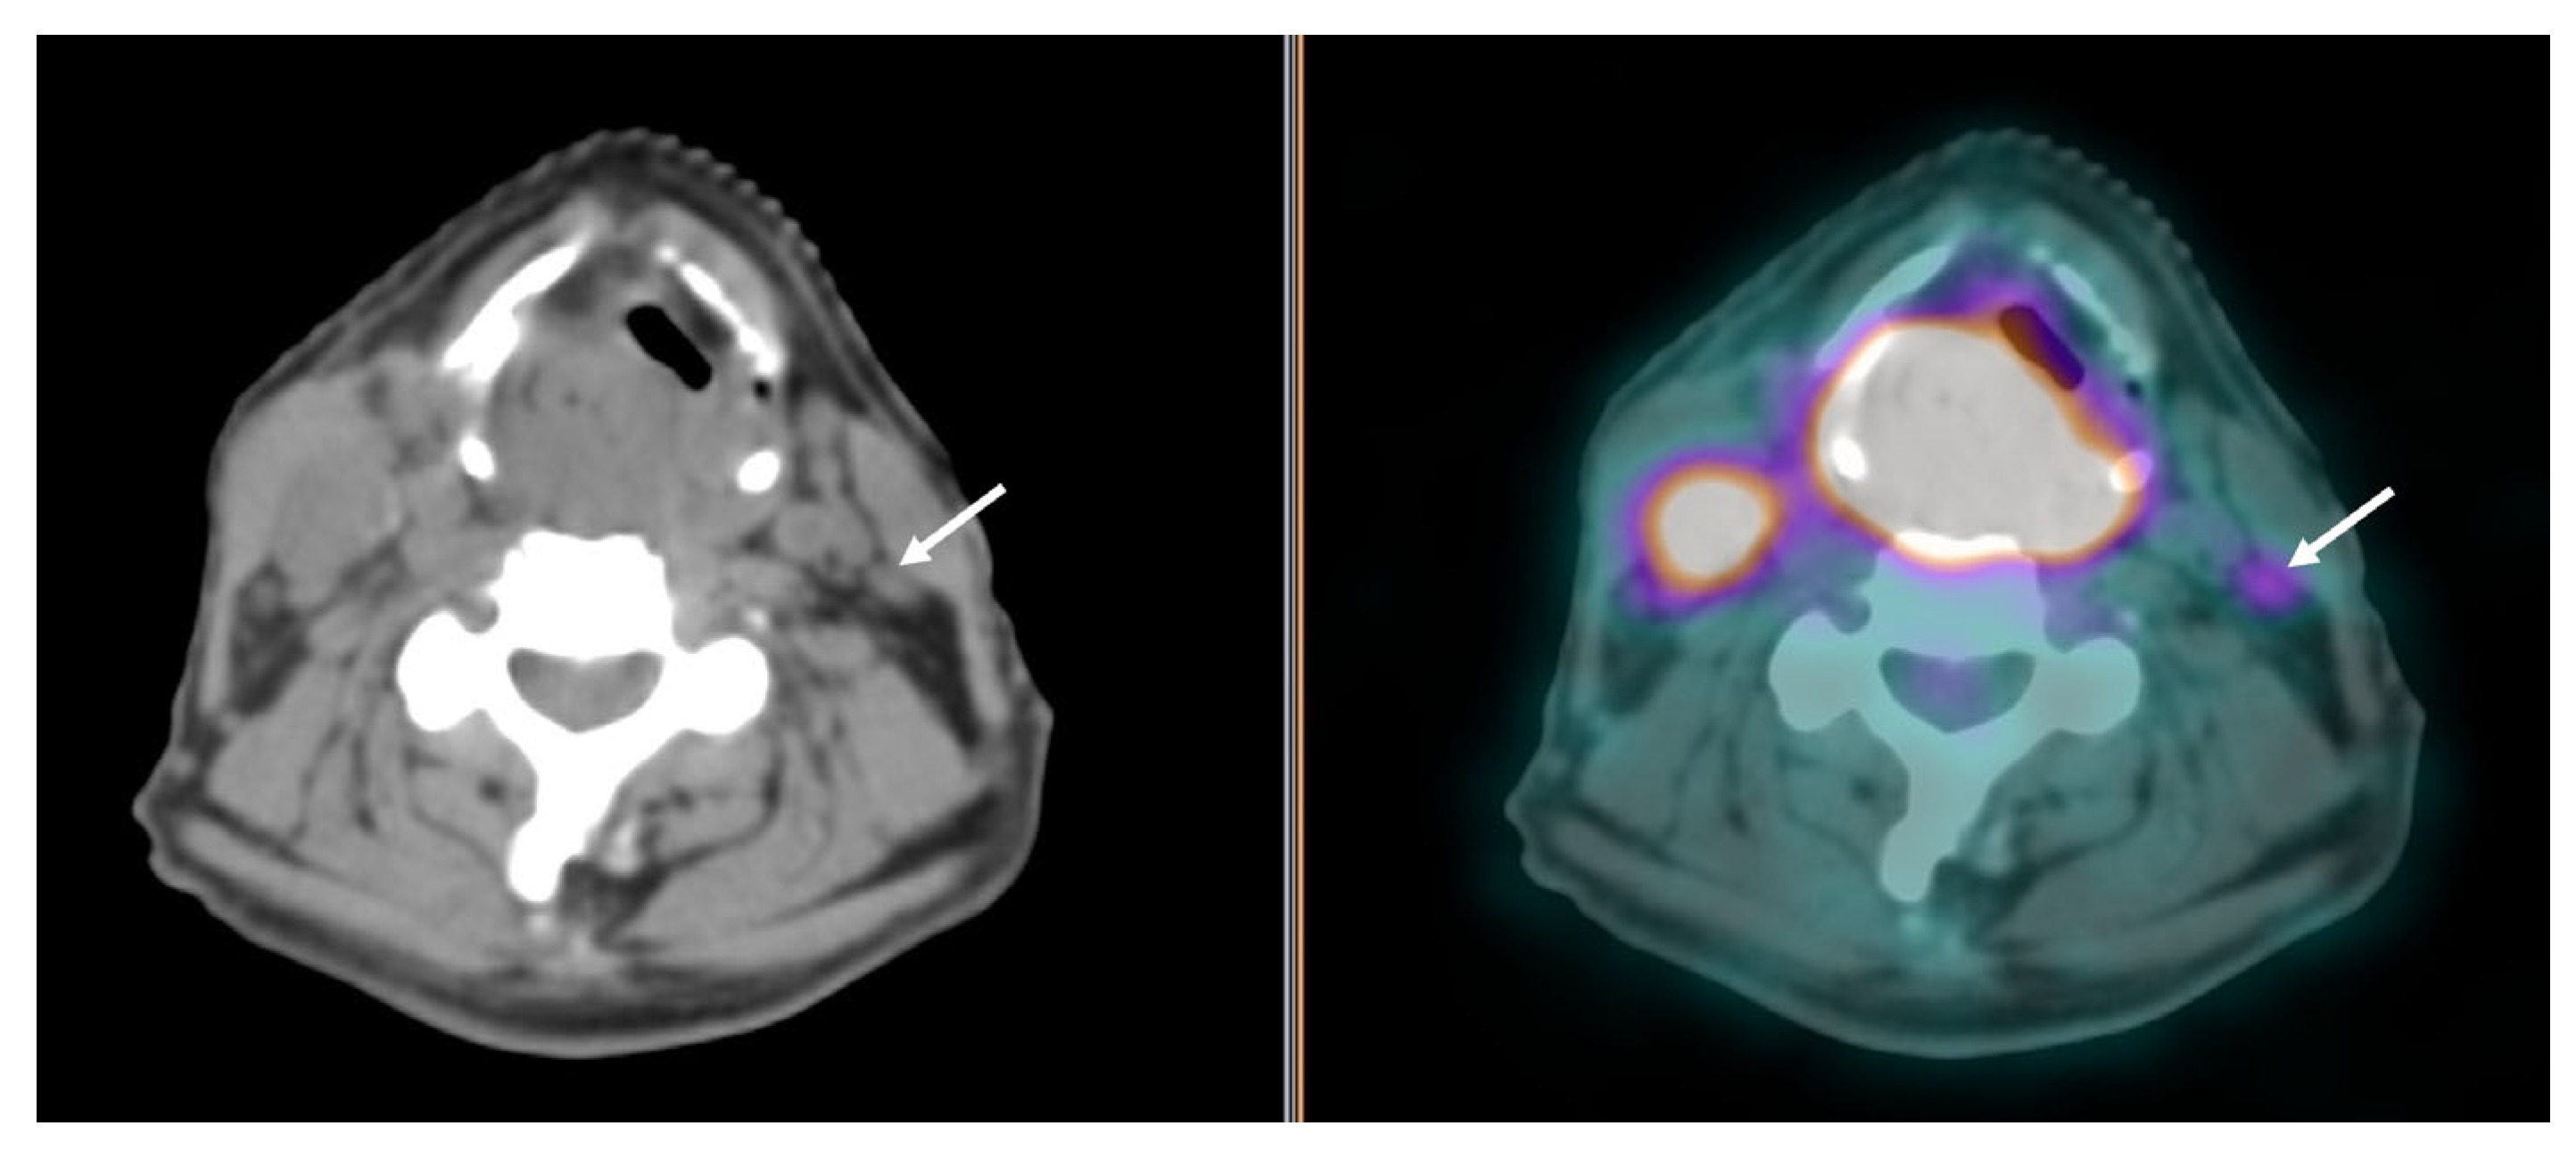

| Selection and delineation of GTV | - Detection of occult primary tumor (see text) - Tumor extension not defined on CT or MRI (see Figure 3) |